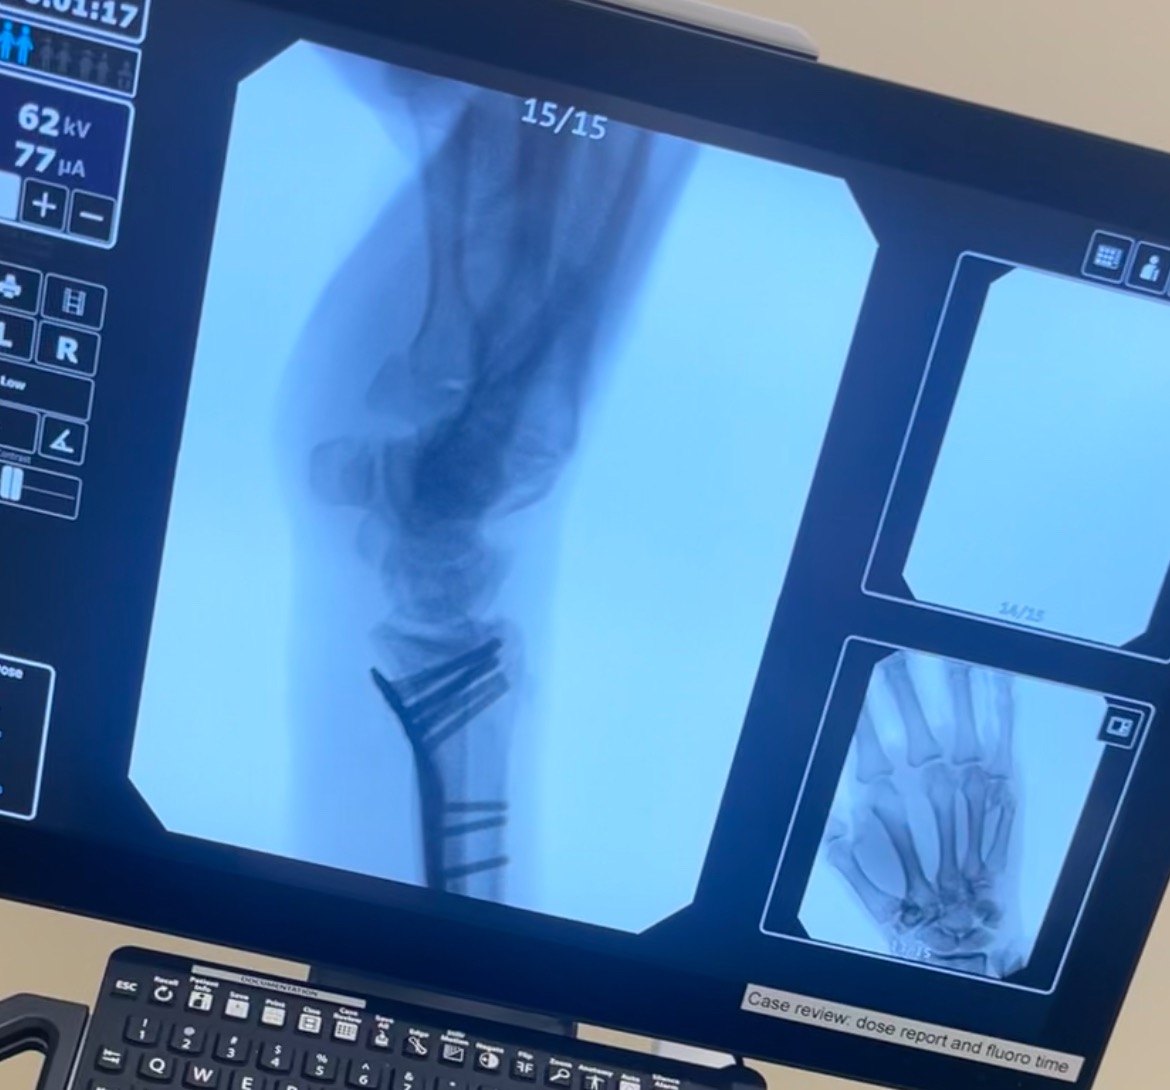

The injury turned out to be far worse than a simple break. On August 22nd, I underwent major surgery. Surgeons had to put my wrist back together with eight pins and two plates, even pinning the head of my radius back on. The recovery has been painful, slow, and overwhelming.